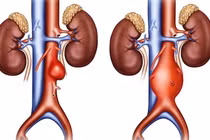

Người bệnh nam, 75 tuổi, nhập viện lúc nửa đêm trong tình trạng đau bụng dữ dội, huyết động không ổn định. Qua thăm khám lâm sàng và hình ảnh chụp cắt lớp vi tính (CLVT), các bác sĩ xác định người bệnh bị vỡ phình động mạch chủ bụng kèm khối máu tụ lớn trong ổ bụng, đe dọa trực tiếp đến tính mạng.

chu-bung.png

Hình ảnh khối máu tụ do vỡ động mạch chủ bụng trên phim chụp CLVT và sau khi mở bụng - Ảnh BVCC